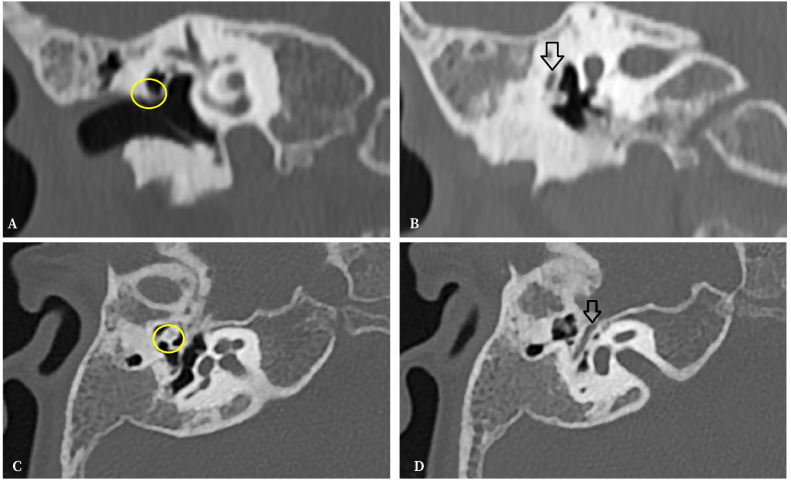

Goldenhar syndrome is a rare congenital disorder characterized by defects in the development of structures derived from the first and the second branchial arches. This condition encompasses a range of symptoms, including craniofacial, ocular, vertebral, and auricular abnormalities. We present the case of a 6-year-old girl with right temporal bone hypoplasia and preauricular tag from birth, leading to a diagnosis of Goldenhar syndrome. She exhibited various middle and external ear defects, and her audiological treatment was crucial in ensuring optimal neurological and speech development. In adolescence, if the Eustachian tube remains stable, surgical repair of the ossicular chain may be considered.